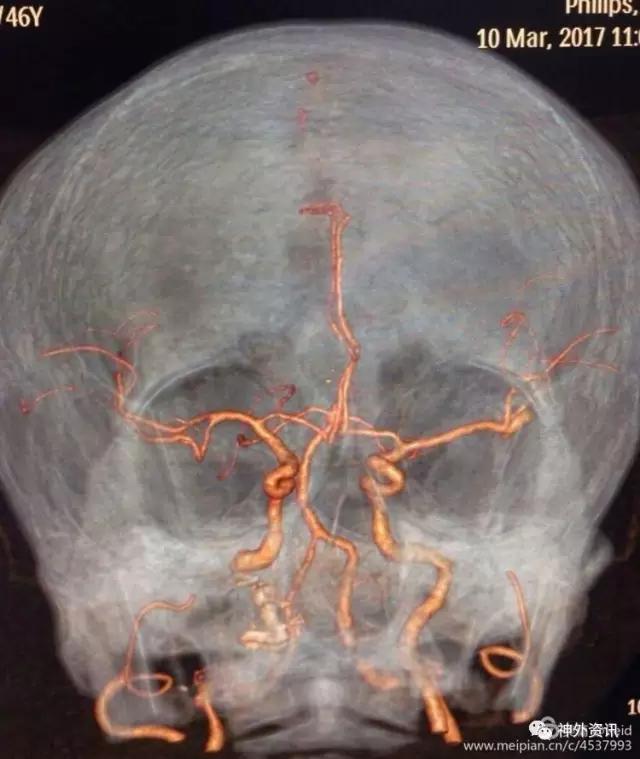

CTA提示基底动脉尖不规则形状动脉瘤,同时左侧大脑中动脉M1末端囊状动脉瘤。

重点显示基底动脉尖动脉瘤和大脑中动脉动脉瘤形态和颅骨表面投影。